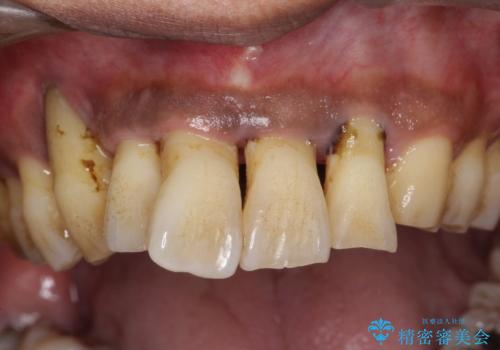

- 歯並びが気になり矯正をしたいと来院された。歯周病の検査、レントゲンをとり重度の歯周病であることがわかりました。

まずは、歯周病の初期治療から行っていくことを説明。

黒々とした厚みのある歯石が歯の表面に沢山付いていました。

痛みもなかったため(冷たいものでしみる知覚過敏症状はある)びっくりされていた印象です。